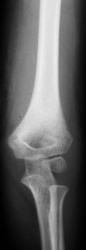

Пол пациента: Мужской пол Тип патологии: Травма Область исследования: Скелетно-мышечная система Методы исследования: Rg Рентгенограммы произведены в "ургентном" порядке ургентным лаборантом. Пациент направлен на исследование дежулным хирургом. ВАШЕ МНЕНИЕ КОЛЛЕГИ? TRAVMA.1..JPG TRAVMA_2..jpg TRAVMA.3..jpg TRAVMA.4..JPG TRAVMA.5..JPG AttachmentSize TRAVMA.1..JPG45.46 KB TRAVMA_2..jpg78.72 KB TRAVMA.3..jpg82 KB TRAVMA.4..JPG57.79 KB TRAVMA.5..JPG76.83 KB Mon, 16/11/2009 - 18:06 #1 v1tal Offline Last seen: 4 years 10 months ago Joined: 07.06.2008 - 19:41 Posts: 1779 Супракондилярный перелом дистального эпифиза плечевой кости, с незначительным угловым смещением открытым кзади. "Знаешь, у некоторых врачей есть комплекс мессии — им необходимо спасать мир. А у тебя комплекс Рубика — тебе необходимо решать головоломки." Mon, 16/11/2009 - 22:39 #2 В.Б. Серов Offline Last seen: 3 weeks 6 days ago Joined: 16.07.2008 - 10:15 Posts: 1361 Перелом вижу, смещения - нет Зри в корень! Mon, 16/11/2009 - 23:06 #3 Анатолий Владим... Offline Last seen: 7 years 10 months ago Joined: 16.10.2009 - 21:16 Posts: 1941 А смещение действительно минимальное.

Супракондилярный перелом дистального эпифиза плечевой кости, с незначительным угловым смещением открытым кзади.

Перелом вижу, смещения - нет

А смещение действительно минимальное.